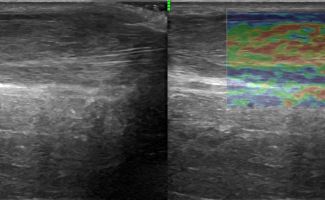

Foot Tendons

Foot Ultrasound allows the diagnosis of tendonitis, tenosynovitis, and rupture in the following tendons:

- Achilles Tendon

- Peroneal Tendons

- Flexor Tendons

- Extensor Tendons